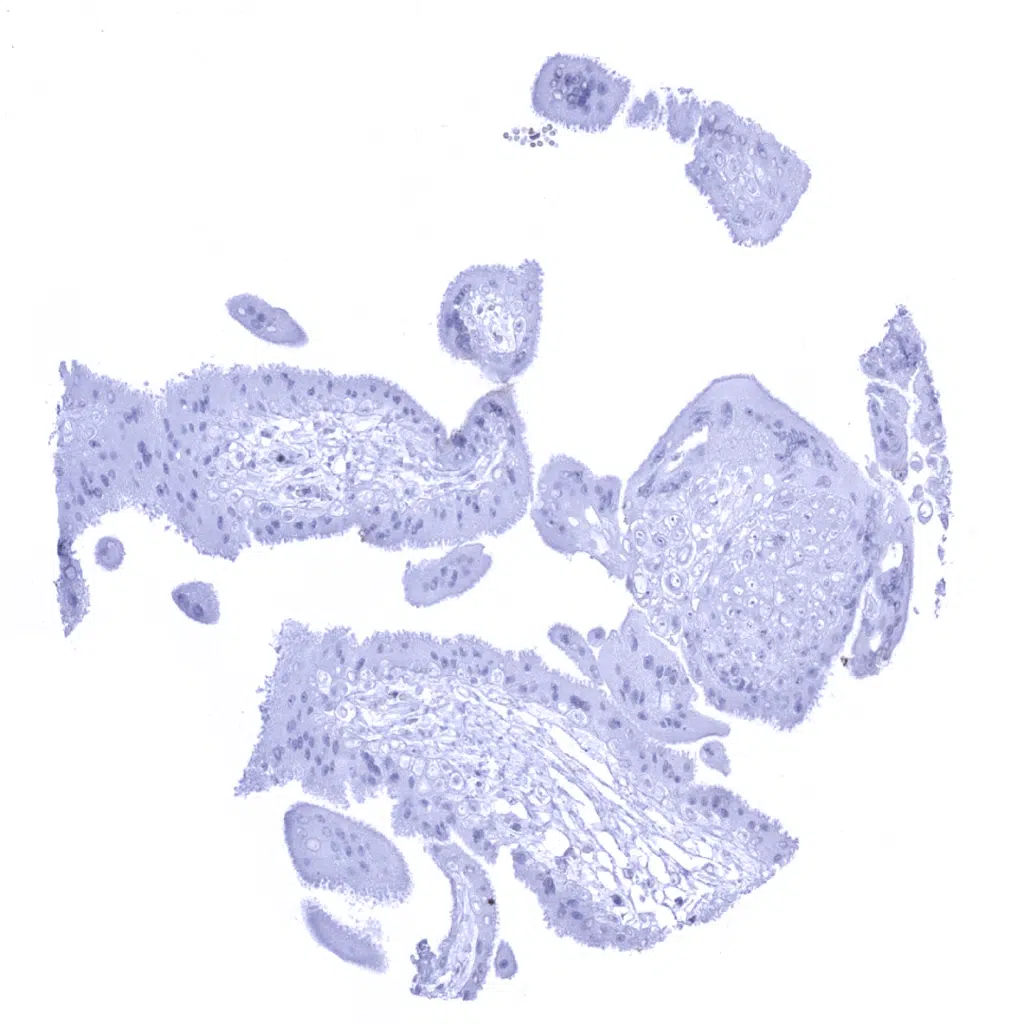

Esophagus, squamous epithelium – Membranous Dsg3 immunostaining is predominantly seen in basal and suprabasal squamous epithelial cells.